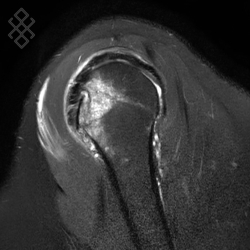

Arthro-IRM de l’Épaule

La durée de l'examen est d'environ 20 minutes. Pour repérer la zone souahitée, le radiologue fera une scopie. Ensuite, il effectuera une désinfection puis une anesthésie locale. Pour l'injection du produit de contraste à base de gadolinium, il introduira une aiguille dans la zone repérée, puis il appliquera un pansement étanche. Enfin, vous serez installés afin d'effectuer l'IRM de l'épaule.